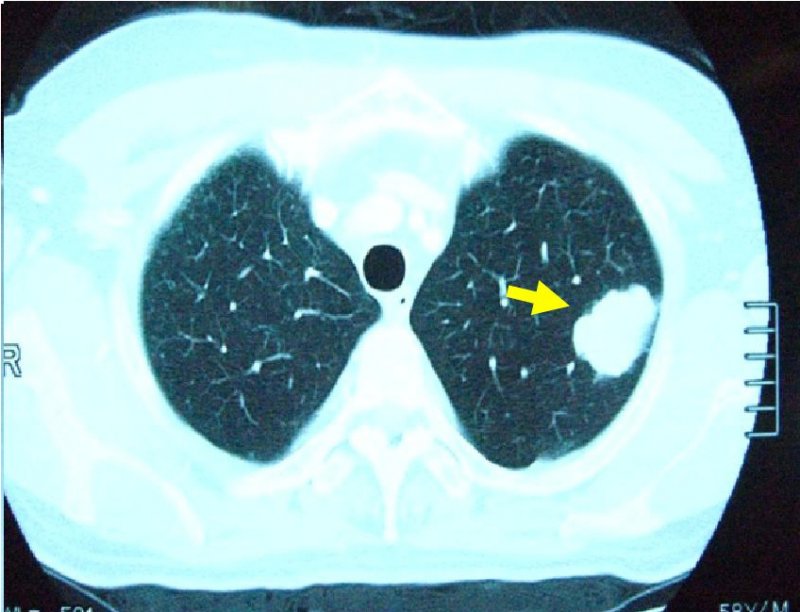

左肺癌の画像所見

胸部XP(左上肺野に腫瘤影あり)

胸部CT